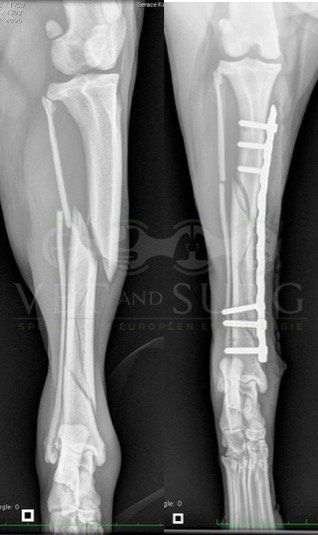

A la radiographie, une fracture de type Salter-harris 1 est diagnostiquée, avec déplacement de l'about discal.

Une réduction de la fracture par pose de 2 broches en croix a été réalisée.